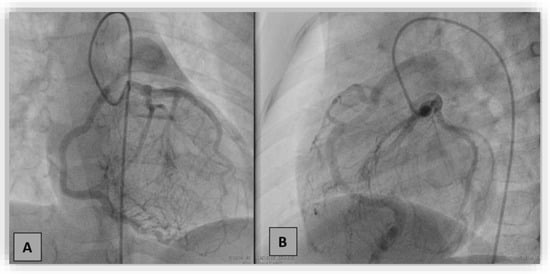

3. Case Report #2